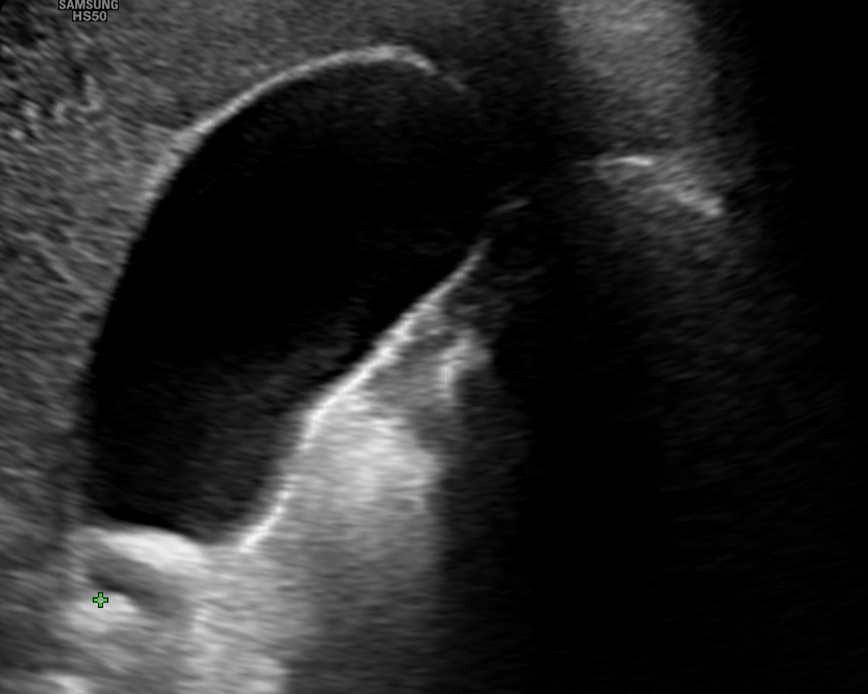

- Estudio de la vesicular biliar y vías biliares